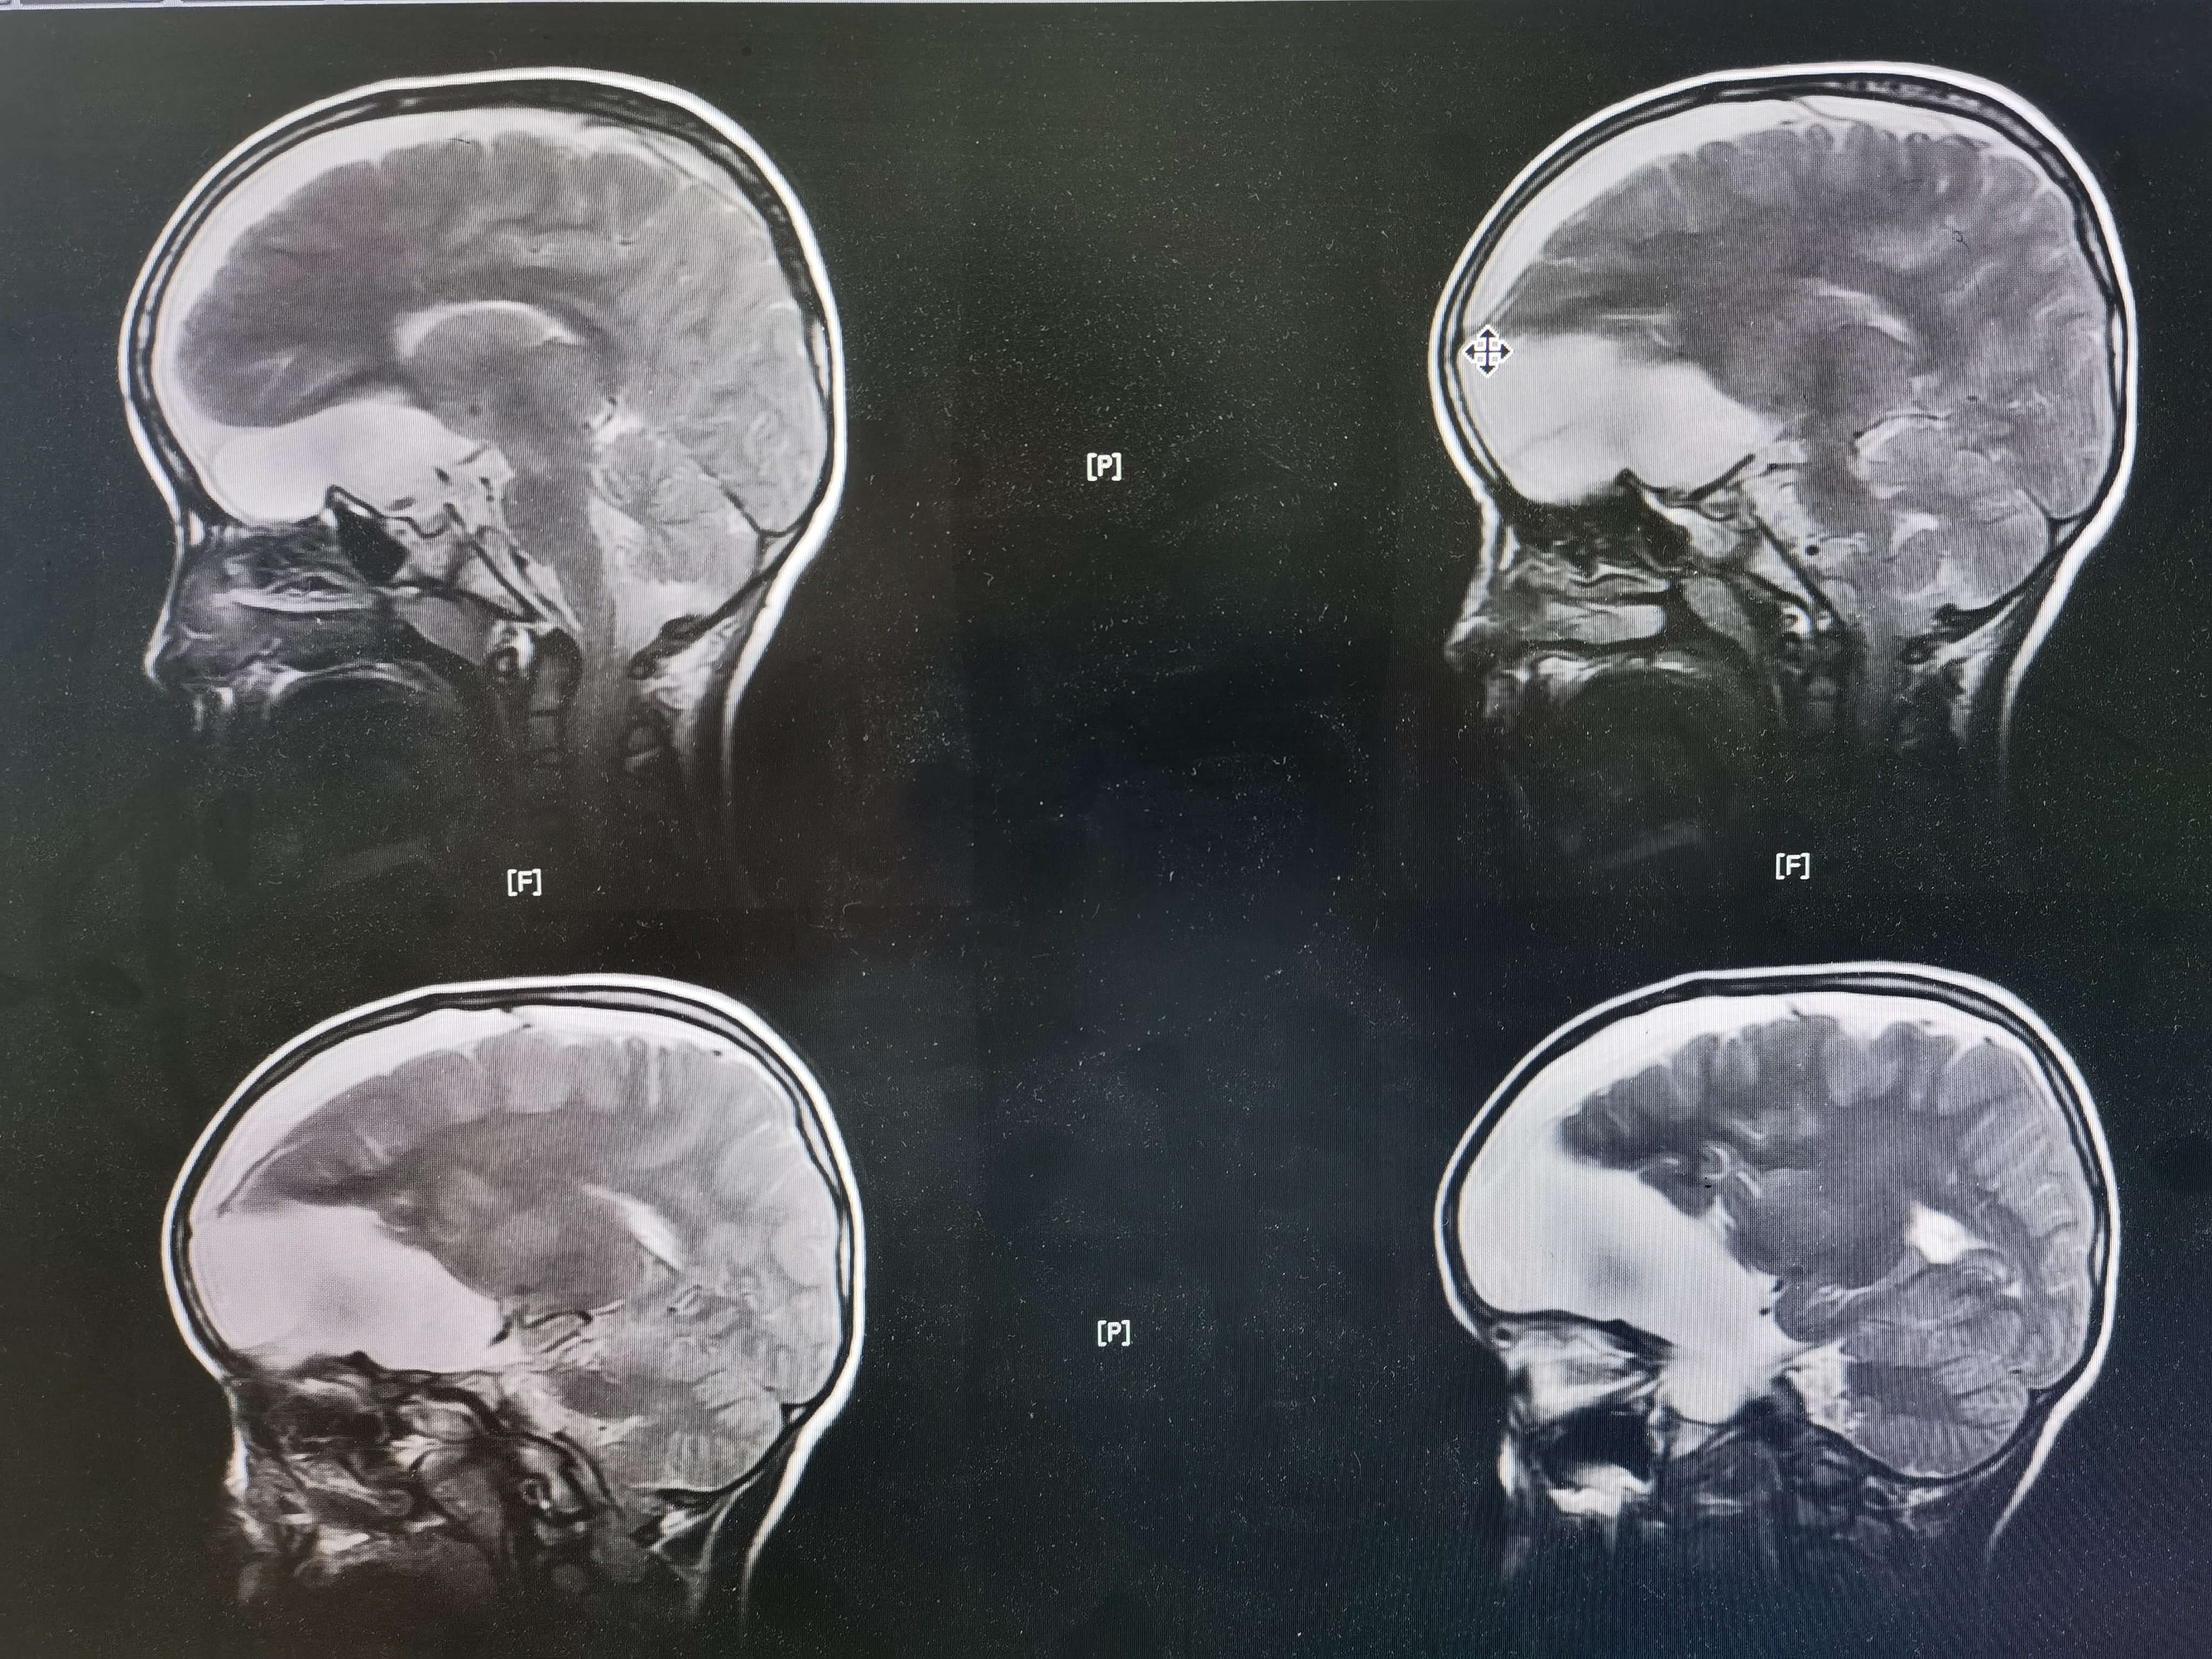

8岁男孩,以“头部外伤后头晕8天”入院,患儿8天前于3米高处坠落摔伤头部,伤后有昏迷史,当地医院CT提示左额颞巨大蛛网膜囊肿,破裂可能。患儿伤后感头晕,当地医院建议转至我院。我院完善头颅MR提示左额颞巨大蛛网膜囊肿,局部越过中线突入右侧镰旁挤压右额叶,左侧额颞岛叶明显受压,囊肿破裂可能。

术前MR